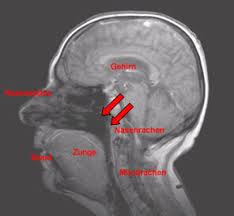

Polypen können Hörvermögen bei Kindern stark einschränken.

Dazu gehören meistens körperliche Beeinträchtigungen wie schlechtes Hörvermögen durch Polypen frühere Hirnhautentzündungen oder Probleme mit Mund und Lippen. Polypen können Hörvermögen bei Kindern stark einschränken. Bei der Entfernung der Rachenmandeln Adenotomie handelt es sich um einen Standardeingriff der rund 20 Minuten andauert. Dazu gehören meistens körperliche Beeinträchtigungen wie schlechtes Hörvermögen durch Polypen frühere Hirnhautentzündungen oder Probleme mit Mund und Lippen. Die ständige Mundatmung mit offen stehendem Mund und viel Speichelbildung ist in der Regel Folge einer länger bestehenden Nasenatmungsbehinderung. Nasenpolypen sind in der Regel gutartige Geschwülste. Voraussetzung für eine altersgerechte Sprachentwicklung bei Kindern ist zunächst ein gutes Hörvermögen sowie eine altersgemäße körperliche und mentale Entwicklung. Sie können allerdings abhängig von der Größe die Atmung behindern und Beschwerden wie Kopfschmerzen Schnarchen oder Entzündungen der Nasennebenhöhle und des Mittelohrs verursachen. Müssen vergrößerte Polypen immer operiert werden.

Voraussetzung für eine altersgerechte Sprachentwicklung bei Kindern ist zunächst ein gutes Hörvermögen sowie eine altersgemäße körperliche und mentale Entwicklung. Lebensjahr und operiert wurde er mit 2 Jahren 8 Monaten. Entdecken Sie Ihre neue Nähmaschine passend für Ihre Anforderungen. Allerdings muss das Mittel nach den individuellen Symptomen Ihres Kindes sehr genau ausgewählt werden. Ebenso zu den Polypen Symptomen beim Kind gehören nächtliche Atemaussetzer. Sollten bei der U7 hier Auffälligkeiten auftreten wird euch der Kinderarzt an. Startseite Pädaudiologie Phoniatrie Sprachentwicklung.